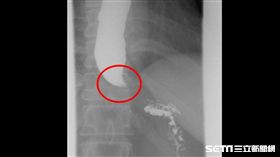

她慘變紙片人!食道攝影嚇見「鳥嘴」

高雄一名16歲女高中生,半年前開始只要一吃完東西就必...